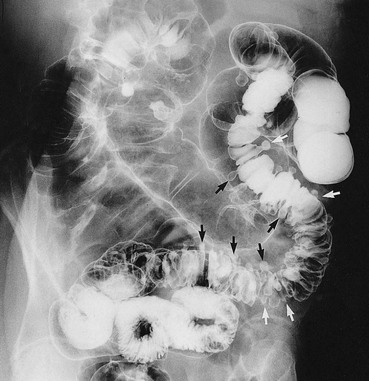

The consequences of diverticular inflammation are collectively described as diverticulitis and are summarised in Figure 29.3. Most people with diverticula are asymptomatic, and diverticula are a common incidental finding when the colon is investigated by barium enema or colonoscopy. Typical appearances are shown in Figures 29.2 and Fig. 29.4.

Fig. 29.2 Diverticular disease

Barium enema showing the typical appearance of multiple diverticula (arrowed) in the sigmoid and descending colon in a 77-year-old woman. A few diverticula are also present in the transverse colon